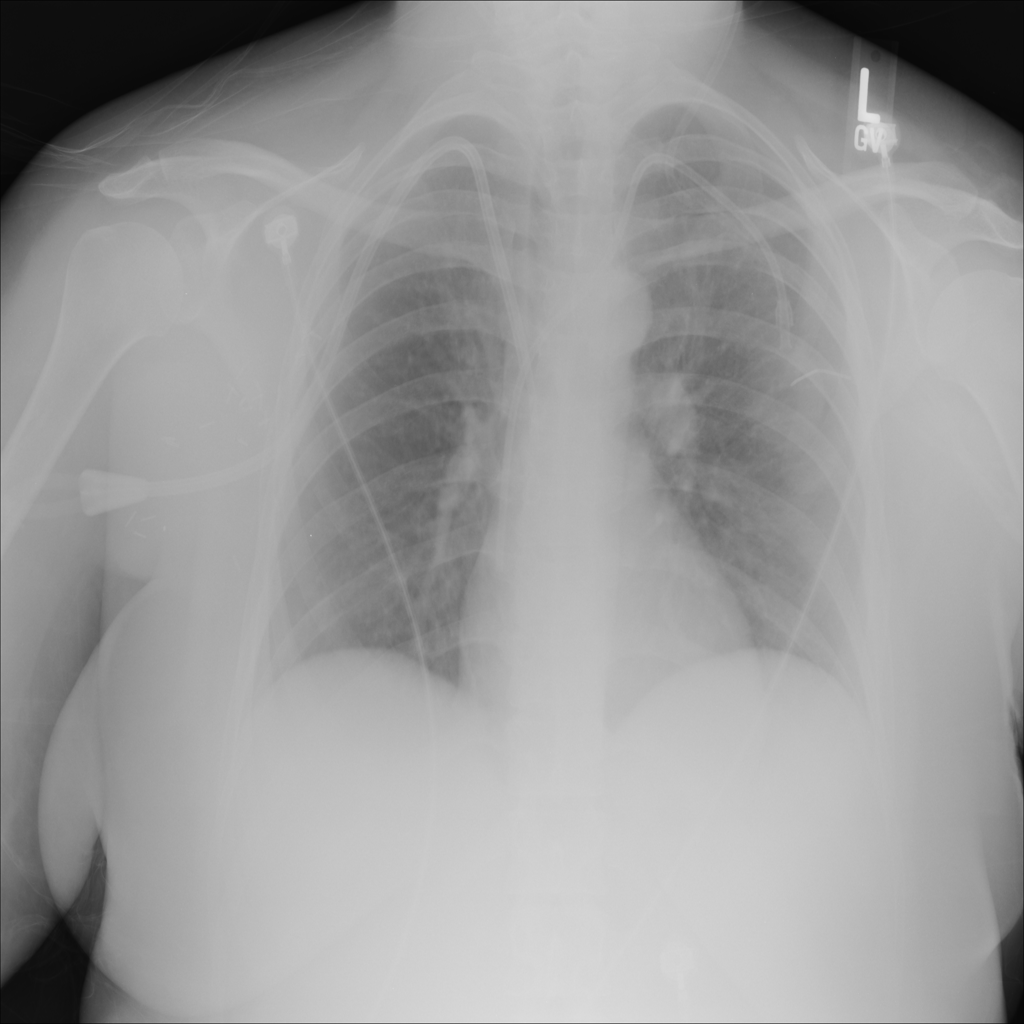

PAT-24D9 · IMG-006Edema

PAT-24D9 · IMG-006

AP